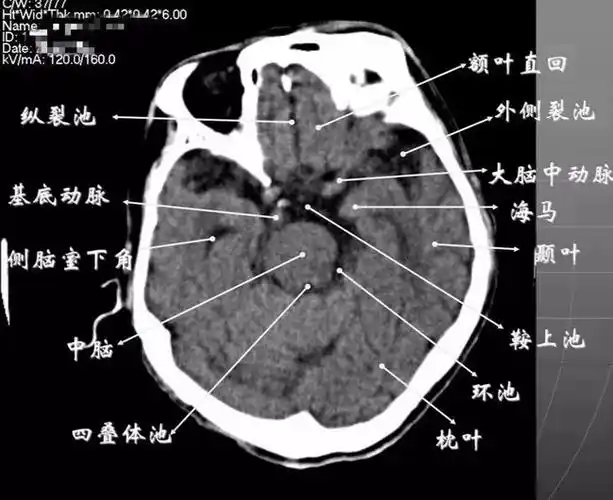

读懂头颅ct并不难,教你成为读片小能手